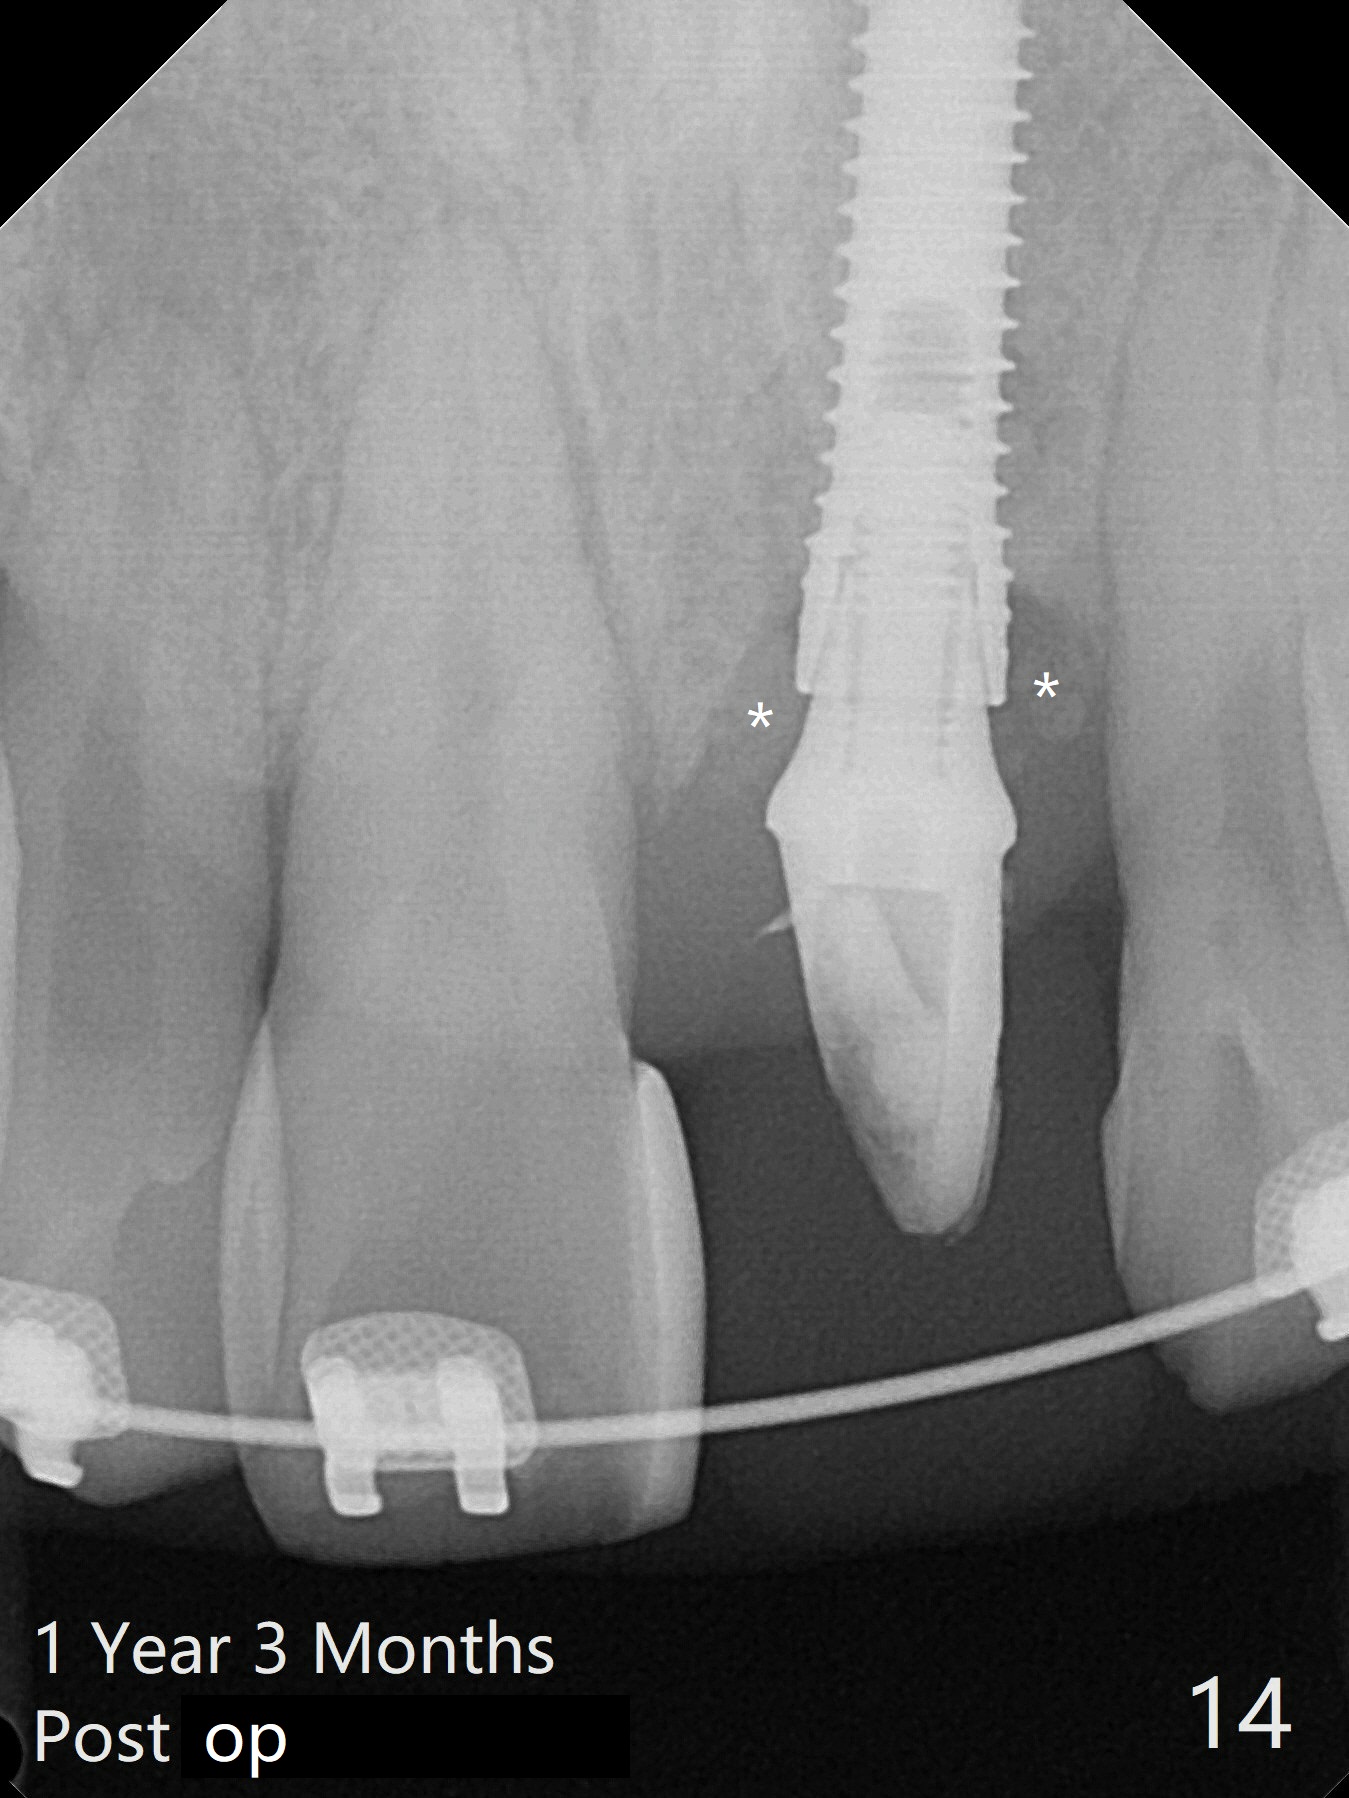

Nearly 7 months postop, the immediate provisional at UL1 is removed; with the mesial reduction of UL2 from 7 to 6 mm (Fig.1), an angled abutment is to be changed (4.5x15 degree, 2 mm cuff). A new provisional (Fig.2,3) co-incides with the facial midline. Brackets will be placed between UR4 to UL3 except UL2 (symptomatic once with chronic periodontitis) with initial proximal reduction between UR1-4 in preparation to correct cross bite of UR2. Twelve days later, the patient returns for UR5-UL3 bracketing after UR1-4 initial proximal reduction with 14 niti wire (Fig.4-6). UR1 moves mesial 20 days post open coil spring (Fig.7 arrow), while UL1 debracketes after permanent re-cementation of the temporary crown last visit (*, no re-bracketing, since it appears not essential). Before placement of 20 ss wire, diastemata are created by proximal reduction (Fig.8 *). In fact UR1 moves mesial, while UR3 does not move distal with the open coil. With placement of UR6 (implant) molar band, UR3 is distalized effectively. With sling shot, UR2 is almost labialized in one appointment (Fig.9). After consolidation of the diastemata between UR1-6 with power chains following UR2 cross bite correction (Fig.10), the restoration space for UL1 seems to be too large (Fig.11). Next visit, check the midlines, take 1-2 PAs for #7-9 and determine whether a straight abutment should be changed back and whether composite should be placed UR1 mesial to reduce the space. One week later, composite is added to the mesial surface of the tooth #8 to increase its width, while the provisional at #9 is relined to improve the interdental papilla (Fig.12). Minimal bone loss at UR2 is observed 8 months post banding (Fig.13), while the socket at UL1 seems to have healed except the most coronal 1 year 3 months postop (Fig.14 *). The margin of the abutment should be uneven, more coronal proximal than buccopalatal (Fig.15). The final crown has an open margin, partially due to less ideal trajectory (Fig.16 (black line: ideal trajectory, nearly 1 year 4 months postop)). Guided surgery could solve the problem. Sticky bone may restore the buccal plate defect. Die shows that the implant is palatally placed (Fig.17). CT will be taken to determine whether the implant perforates the palatal plate.